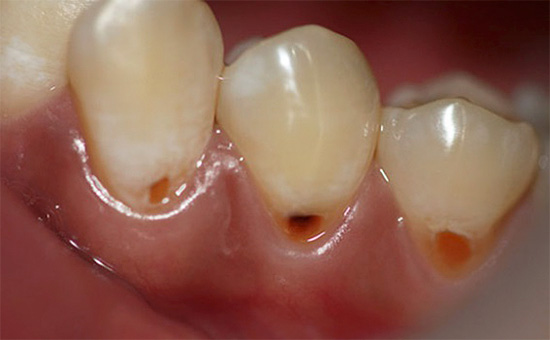

As cavidades cariosas do colo do útero se desenvolvem apenas perto da margem gengival tanto na superfície vestibular quanto nas superfícies labiais do esmalte. Ou seja, são áreas visíveis aos olhos.

A foto abaixo mostra uma comparação de cárie cervical com cárie radicular:

Quanto à cárie basal, é formada ao longo das raízes expostas dos dentes nas superfícies lingual, de contato e bucal. Isso significa que, neste caso, também podemos ver com os olhos as áreas de cárie dentária.